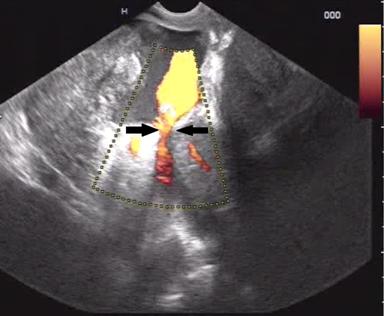

A 32 year old male patient diagnosed as alcohol related acute necrotising pancreatitis (ANP) 2 months ago, now presented with abdominal pain and early satiety. Contrast enhanced computerized tomography (CECT) showed 12 cm walled off pancreatic necrosis (WOPN) (Figure 1). Endoscopic ultrasound (EUS) revealed large WOPN and power doppler revealed vascularity in collection with pulsatile flow suggestive of blood leaking into collection (Figure 2). However, no abnormal vessel or pseudoaneurysm could be identified. CT angiography (CTA) also showed normal major abdominal arteries (Figure 3). Since patient was symptomatic, after informed consent EUS guided transmural drainage was attempted. Now there was no vascularity in collection and procedure was successfully accomplished. A 7 Fr nasocystic drain (NCD) was inserted and it drained purulent material. Patient had marked symptomatic relief but 6 hours later had severe pain and hematemesis with blood coming through NCD also. CTA revealed blood in WOPN but no abnormal bleeding vessel was identified (Figure 4). Digital subtraction angiography (DSA) also did not reveal any abnormal or bleeding vessel. The patient was managed with blood transfusion and NCD was kept patent by intermittent flushing. The bleeding subsided and the effluent from NCD cleared in 48 hours. The NCD was replaced with 10 Fr pigtail stents and CT abdomen done 3 weeks later revealed resolution of WOPN (Figure 5). The patient has been asymptomatic over a follow up period of 13 months.

Figure 2. EUS: Power Doppler showing vascularity in collection. The blood can be seen leaking into collection (arrow). |